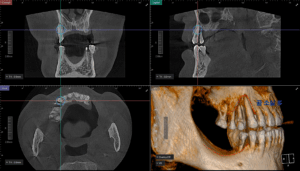

임플란트 식립을 위해서는

3D CT 사진을 촬영하여

더 자세히 보아야 하는데요.

평면적인 사진과 같이

뼈가 많이 녹아있는 것을

볼 수 있습니다.

먼저 컴퓨터 분석을 통해

식립 할 위치를

정밀히 분석하였습니다.